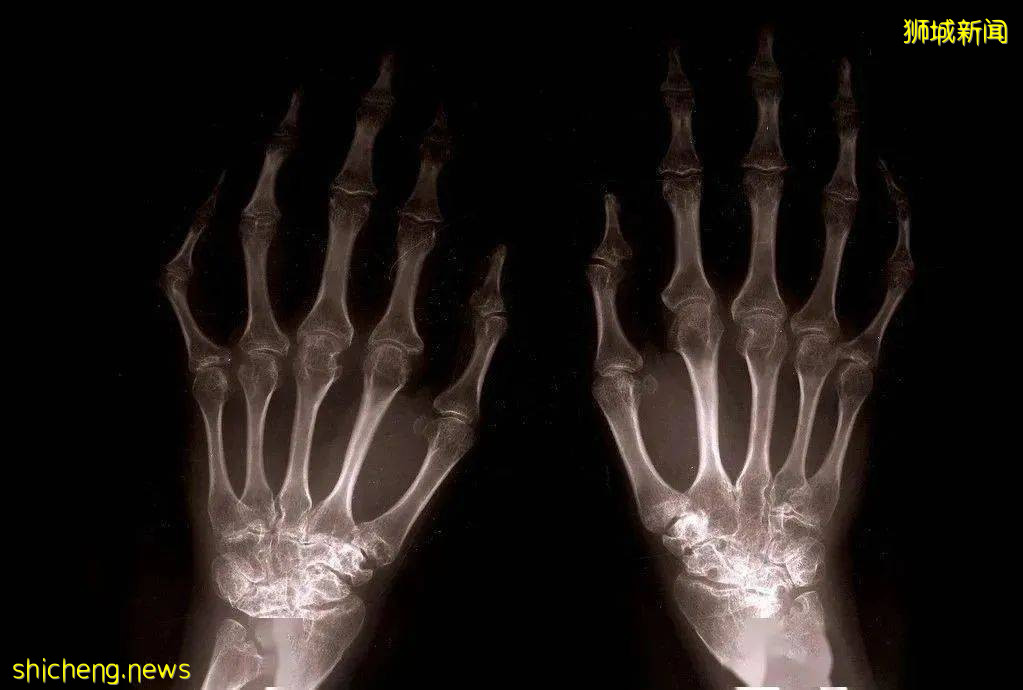

类风湿关节炎的诊断必须结合临床评估。

医生会检查关节是否肿胀,检测发炎指标以及风湿因子等等。

少数情况下,医生可以运用超音波诊断出类风湿关节炎。